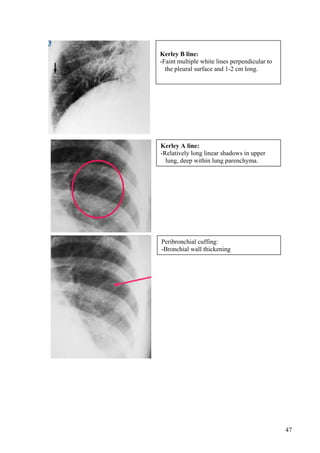

6.1 Pulmonary interstitial edema

- Kerley B lines

- Kerley A lines (Kerley–thicken

connective tissue septa )

- Peribronchial cuffing: thicken

bronchial wall and peribronchial

sheath.

- Thickening of the fissures

- Pleural effusion

- Perihilar haze: blurring of hilar

shadows.

- Blurring of pulmonary vascular

markings

Kerley B line:

-Faint multiple white lines perpendicular to

the pleural surface and 1-2 cm long.

Kerley A line:

-Relatively long linear shadows in upper

lung, deep within lung parenchyma.

Peribronchial cuffing:

-Bronchial wall thickening